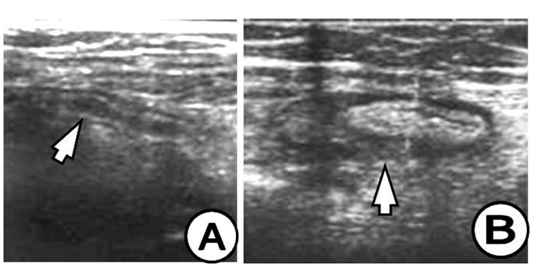

The appendix on US study is demonstrated by: hypo echoic lumen, hyper echoic mucosa, iso echoic lamina propria, hyper echoic submucosa, hypo echoic muskularis and hyper echoic serosa. The increased size of the appendix is a sign for phlegmonous or gangrenous appendicitis (Figure 1). The present appendicolith is demonstrated as hyper echoic mass that fills in the lumen and gives acoustic shadow (Figure 2B). When the appendicolith should be visualized, the wall thickness and the compressibility are not the features for making the diagnosis of acute appendicitis. The gangrenous appendicitis has changes in echogenity in all layers and the same are with the uniform echogenity and cannot be distinguished (Figure 3A). If the ill defined or hypo echoic mass is seen that surrounds the appendix that presents the periappendiceal inflammation (Figure 4). The ill defined appendiceal wall is suggestible, but not diagnostic for the periappendiceal process. The fluid presence into the appendiceal surrounding, with appendiceal wall echogenity changes is US feature for perforation (Figure 3B). The positive lymph nodes are oval hypo echoic and they don’t change the shape on compression.

Figure 3 (A) Appendix in saggital and coronal plane, thicken and oedematous wall, with widen lumen, disturbed appendiceal architecture and surrounding infiltration, US finding for gangrenous appendicitis, (B) Appendix with thickened wall, widened lumen and periappendiceal fluid, US finding for gangrenous appendicitis.